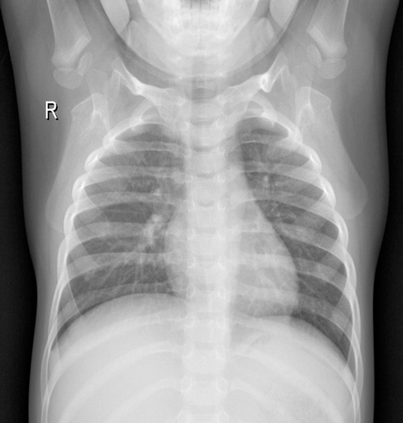

Pneumonia remains a leading cause of morbidity and mortality worldwide. Chest X-ray (CXR) imaging is a fundamental diagnostic tool, but traditional analysis relies on time-intensive expert evaluation. Recently, deep learning has shown immense potential for automating pneumonia detection from CXRs. This paper explores applying neural networks to improve CXR-based pneumonia diagnosis. We developed a novel model fusing Convolution Neural networks (CNN) and Vision Transformer networks via model-level ensembling. Our fusion architecture combines a ResNet34 variant and a Multi-Axis Vision Transformer small model. Both base models are initialized with ImageNet pre-trained weights. The output layers are removed, and features are combined using a flattening layer before final classification. Experiments used the Kaggle pediatric pneumonia dataset containing 1,341 normal and 3,875 pneumonia CXR images. We compared our model against standalone ResNet34, Vision Transformer, and Swin Transformer Tiny baseline models using identical training procedures. Extensive data augmentation, Adam optimization, learning rate warmup, and decay were employed. The fusion model achieved a state-of-the-art accuracy of 94.87%, surpassing the baselines. We also attained excellent sensitivity, specificity, kappa score, and positive predictive value. Confusion matrix analysis confirms fewer misclassifications. The ResNet34 and Vision Transformer combination enables jointly learning robust features from CNNs and Transformer paradigms. This model-level ensemble technique effectively integrates their complementary strengths for enhanced pneumonia classification.